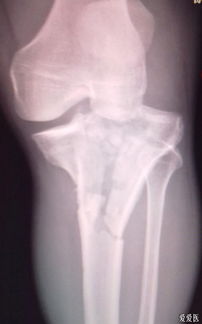

胫骨平台是位于胫骨上端的一个平台,与股骨的髁部形成膝关节。胫骨平台骨折是指胫骨平台部位发生的骨折,可能是由于直接撞击、跌倒或扭伤等原因引起。根据骨折的严重程度和位置,可分为多种类型,如单纯骨折、粉碎性骨折等。

并非所有胫骨平台骨折都适合保守治疗。以下情况可以考虑采用保守治疗:

无移位的胫骨平台骨折

胫骨平台关节面塌陷小于2mm